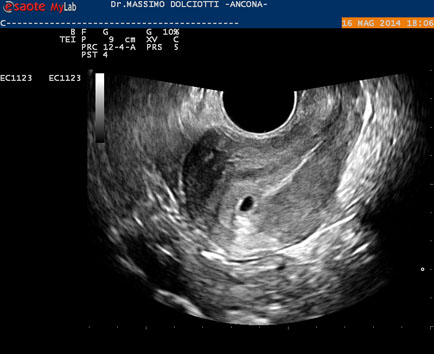

Data inserimento: 19 /05/2014Ecografia del: 16/05/2014 Strumento: Esaote MyLab 50 Gold - Responsabile Linea Cardio Esaote Regione Marche Dr. Franco Fabi Sonda: Endocavitaria Multifrequenza 4-8 MHz Età Paziente: F 27 anni Motivazione dell'esame: amenorrea. Beta HCG = 1.459 mUI/ml. Commento all'esame: le immagini ed il video documentano utero retroverso, con endometrio ispessito e presenza del sacco gestazionale delle dimensioni di 7,6 x 7,2 mm. All'ovaio destro presenza di corpo luteo gravidico con vascolarizzazione aumentata. Conclusioni: gravidanza alla quarta settimana di gestazione (Pregnancy at the fourth week of gestation). Potete esprimere le vostre osservazioni e commenti sul BLOG. Presentazione: Dr. Massimo Dolciotti - Ancona Elaborazione digitale: Andrea Dini - Ancona